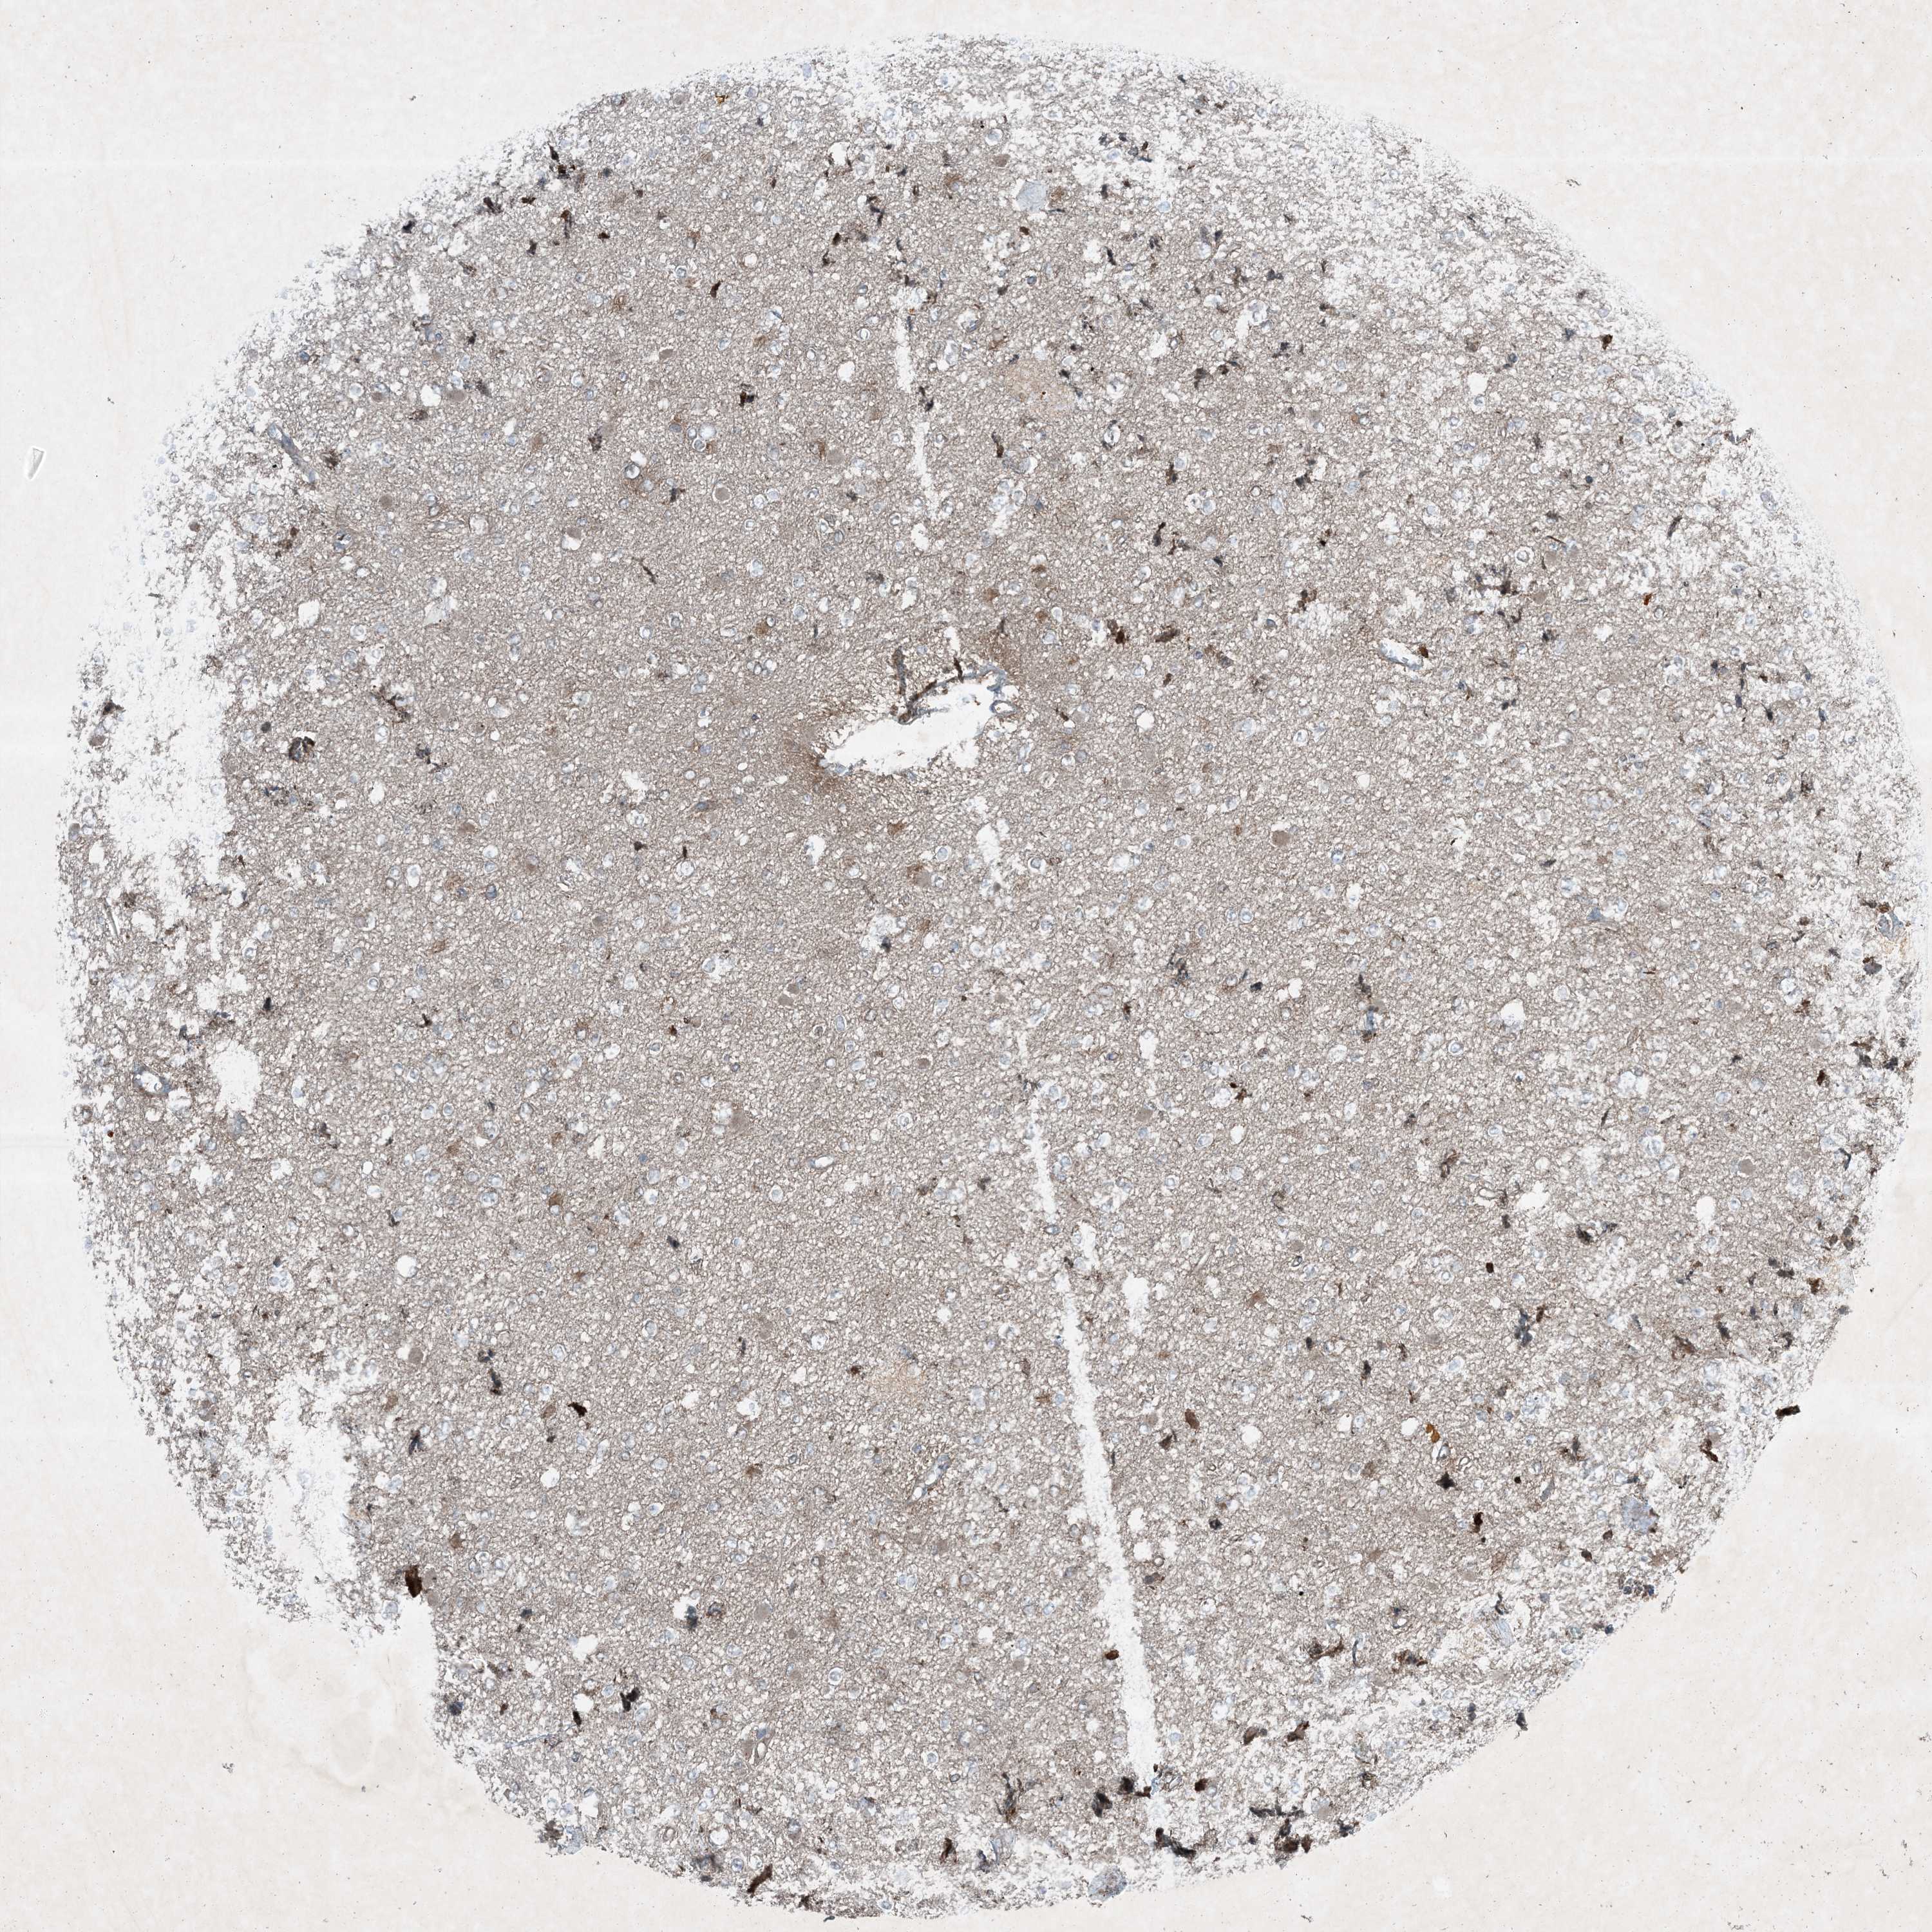

GLIOMA - Protein expressioni

A mouse-over function shows sample information and annotation data. Click on an image to view it in a full screen mode. Samples can be filtered based on level of antibody staining by selecting one or several of the following categories: high, medium, low and not detected. The assay and annotation is described here.

Note that samples used for immunohistochemistry by the Human Protein Atlas do not correspond to samples in the TCGA dataset.

Antibody stainingi

Antibody staining in the annotated cell types in the current human tissue is reported as not detected, low, medium, or high, based on conventional immunohistochemistry profiling in selected tissues. This score is based on the combination of the staining intensity and fraction of stained cells.

Each image is clickable and will lead to virtual microscopy that enables deeper exploration of all samples and also displays staining intensity scores, fraction scores and subcellular localization as well as patient and tissue information for each sample.

Antibody HPA029666

Antibody HPA029667

Antibody HPA029668

Antibody HPA029669

Glioma, malignant, High grade

Glioma, malignant, Low grade

Glioblastoma, NOS